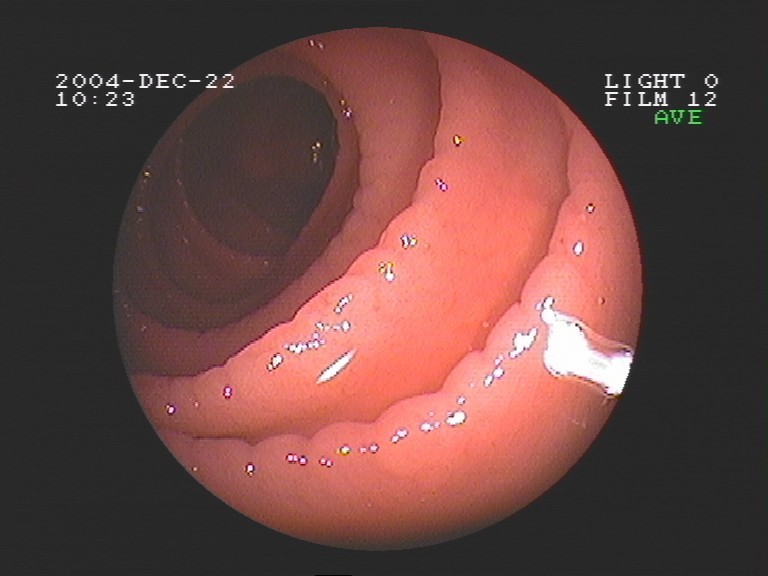

Coloskopie - Dickdarmkarzinom mit deutlicher Stenose (Verengung des Darminnendurchmessers)